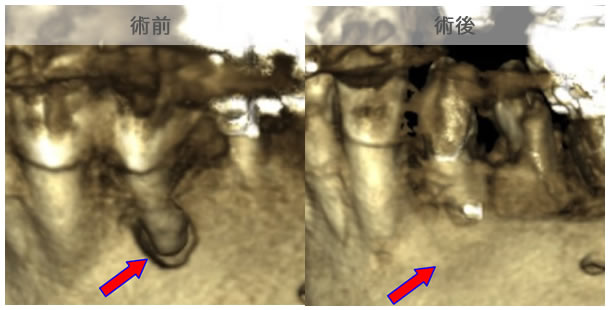

CT画像を見ると根管が2本あることが分かりました。(レントゲンだけでは分かりませんでした。)

| 治療説明 | 右下第2小臼歯、他院で根管治療した後に頬側根尖部から排膿があます。X線CT画像では、根管が2本あり、そのうち舌側が根管充填されていませんでした。顕微鏡下で2根管とも根管充填処置を行い、4ヶ月で、X線透過像は消失しました。 |

|---|---|

| 治療期間 | 6〜24ヶ月 |

| 治療費用 | 150,000〜300,000円 |

| 治療に伴うリスク | 根管内からの治療で根尖病巣が治らない場合は、外科的に根尖病巣を除去する必要があります。 再根管治療を繰り返す場合、歯根の厚みが薄くなり、歯根破折のリスクが高まります。 |